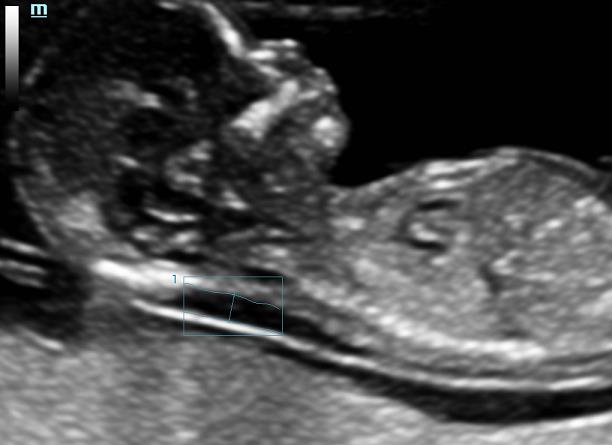

Smart OB/NT

Автоматическое измерение основных параметров фетометрии, включая БПР (обмер и вычисление бипариентального размера головы), ОГ (окружность головы), ДБК (длина бедренной кости), ОЖ (окружность живота), ЛЗР (лобно-затылочный размер головы) и ТВП (толщина воротниковой зоны) доступно с 11 недель беременности и реализуется одним нажатием кнопки – для лучшей повторяемости и воспроизводимости результатов.

resona6_gi11